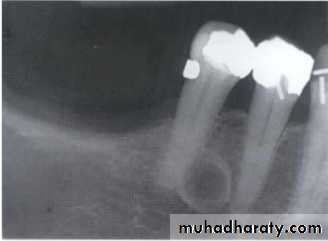

Cystic ameloblastoma displaced IDC (odontogenic origin)

Epicenter coronal to tooth(odontogenic epithelium )